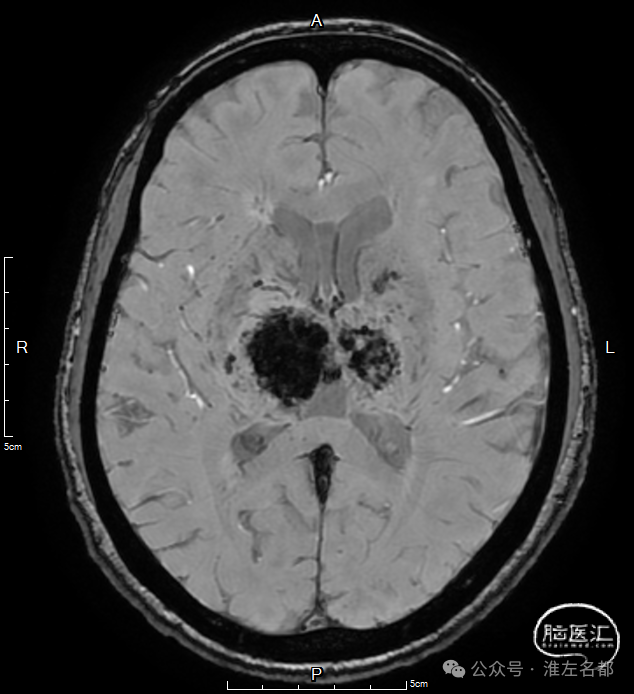

双侧丘脑和右侧内囊-间脑淤血性梗死、水肿和伴渗血。

SWI:双侧丘脑渗血改变,右侧基底静脉和大脑中静脉血栓。